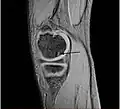

A large flap lesion in the femur head typical of late stage Osteochondritis dissecans. In this case, the lesion was caused by avascular necrosis of the bone just under the cartilage.

Magnetic resonance imaging (MRI) is useful for staging OCD lesions, evaluating the integrity of the joint surface, and distinguishing normal variants of bone formation from OCD by showing bone and cartilage edema in the area of the irregularity. MRI provides information regarding features of the articular cartilage and bone under the cartilage, including edema, fractures, fluid interfaces, articular surface integrity, and fragment displacement.[37][38] A low T1 and high T2 signal at the fragment interface is seen in active lesions. This indicates an unstable lesion or recent microfractures.[30] While MRI and arthroscopy have a close correlation, X-ray films tend to be less inductive of similar MRI results.[38]